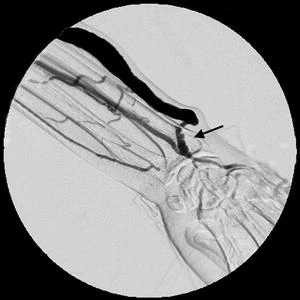

Thrombosis

Aneurysmal degeneration and pseudoaneurysms of AVF/Gs can compromise HD access. A true aneurysm involves dilation of all layers of the vessel wall. Although various definitions exist in the literature and there is not one universally agreed upon, many sources define an aneurysm as a focal enlargement of the vessel diameter exceeding 1.5 to 2 times the caliber of the native mature vein. (Mudoni et al. 2015a) (Shah, Vachharajani, and Agarwal 2013) In contrast, a pseudoaneurysm (false aneurysm) results from a disruption of the vessel wall, blood extravasates from the injury site and is contained by a wall developed with the products of the clotting cascade. (Rivera and Dattilo 2025) Repeated cannulation in the same area is a common cause of pseudoaneurysm formation. Other contributing factors include high-pressure flow, thin or compromised vessel walls, and infection.

Both aneurysms and pseudoaneurysms can compromise vascular access by distorting normal flow and limiting cannulation sites. More concerning are the risks of rupture, infection, and hemorrhage, which can lead to life-threatening emergencies. According to multiple guidelines, urgent surgical consultation is necessary when:

Treatment strategies include aneurysm resection with interposition grafting , primary end-to-end repair or aneurysmorrhaphy. Preventive measures focus on rotating the sites of needle insertion to minimize repeated stress on the same segment of the vessel or graft. Proper cannulation technique, coupled with patient education, can significantly lower the incidence of aneurysm formation.